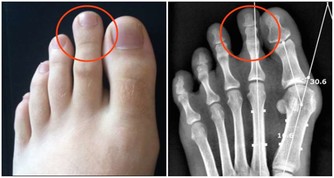

原來「心肌梗塞」不是血管太窄堵阻塞不通!真相竟是?! 醫生現身說法,一定要分享出去!!

原來心肌梗塞不是心臟血管太狹窄堵塞血不流通,請認真看完影片、真的

新光醫院洪惠風醫師解析什麼是"心肌梗塞", 大家抽空看一下喔 ! 值得瞭解。